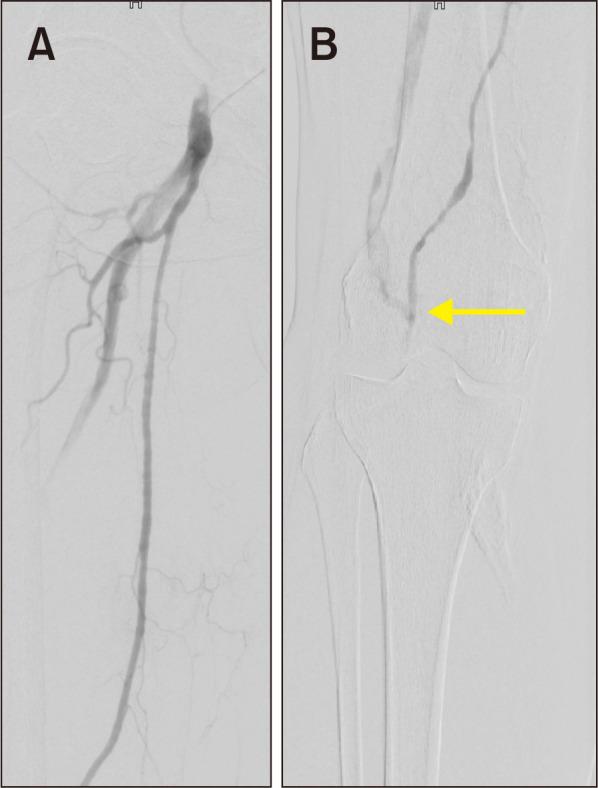

Persistent Sciatic Artery Aneurysm as a Rare Cause of Acute Lower Limb Ischemia.

Vasc Specialist Int. 2022 Mar 31;38:9. doi: 10.5758/vsi.220009.